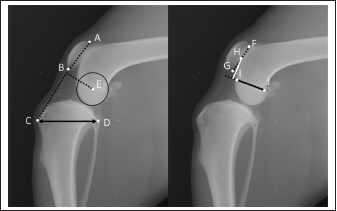

Fig. 2. Measurement method. The patellar length was calculated by dividing the patellar ligament length (distance from point B to C) by the patellar length (distance from point A to B). Tibial width was defined as the distance from point C to D. The PMA was defined as the distance between point E and the intersection point of a perpendicular line from point E to line BC. The distance from the Blumensaat line (line IJ) to the midpoint at the patellofemoral joint of the patella (distance from point F to G) was defined as α (white line). The length of the Blumensaat line (distance from the point I to J) was defined as β (black line). α/β were defined as MBI. A: patella base, B: patella apex, C: tibial tuberosity, D: caudal end of the tibial plateau, E: femoral condyle center, F: the proximal point of the patellofemoral joint of the patella, G: the distal point of the patellofemoral joint of the patella, H: the midpoint at the patellofemoral joint of the patella, I: cranial point of the Blumensaat line, J: caudal point of the Blumensaat line.

Radiographic evaluation

The joint angle, TPA, anatomical-mechanical angle (AMA), PLL:PL, MBI, and PMA were measured from the mediolateral radiographs of the stifle joint (Fig. 2). The joint angle was defined as the angle formed by the anatomical axes of the femur and distal tibia. The AMA was defined as the angle formed by the distal tibial anatomy and the tibial mechanical axis, as Guénégo et al. (2017) reported. Tibial width was defined as the distance from the patellar ligament insertion of the tibia to the caudal end of the tibial plateau. The PLL:PL was calculated by dividing the PLL, which is the length from the most distal point on the patella to the patellar ligament insertion on the tibial tuberosity, by the PL, which is the length from the patella base to the patella apex, as described by Mostafa et al. (2008). The MBI was measured as described by Hanada et al. (2014). The distance from the Blumensaat line to the midpoint at the patellofemoral joint of the patella was defined as α. The length of the Blumensaat line was determined as β. MBI was defined as α/β. PMA was defined as the distance from the center of the femoral condyle to an intersection point of the perpendicular line and from the femoral condyle center to the patellar ligament, as described by Pozzi et al. (2013). We also measured the mechanical medial proximal tibial angle (mMPTA) from the craniocaudal image described by Dismukes et al. (2007).